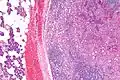

![]() | |

| Micrograph of an acinic cell carcinoma (right of image) and acinar glands (parotid gland - left of image). H&E stain. | |

Histopathologic features

Basophilic, bland cells similar to acinar cells. Growth pattern: solid - acinar cells, microcytic - small cystic spaces mucinous or eosinophilic, papillary-cystic - large cystic lined by epithelium, follicular - similar to thyroid tissue.

These tumors, which resemble serous acinar cells, vary in their behavior from locally aggressive to blatantly malignant.